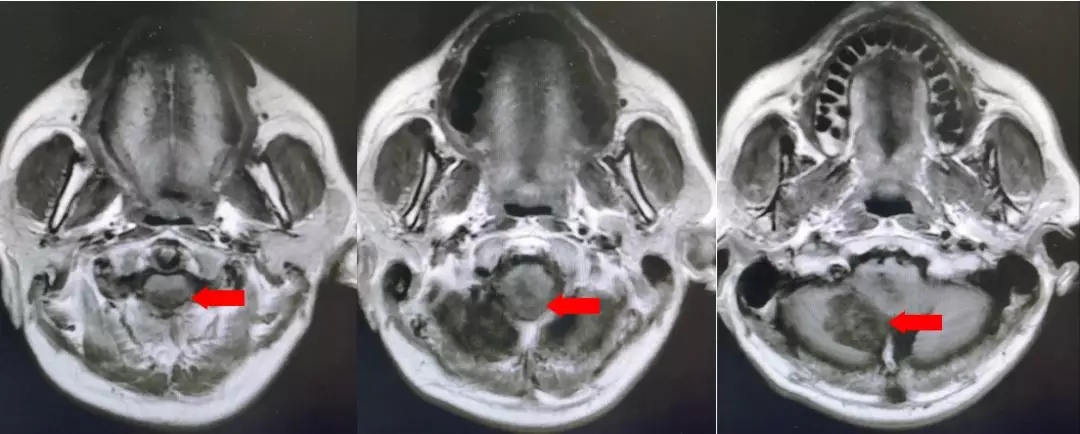

颅脑核磁平扫加增强扫描:

第四脑室内见一巨大形态不规则的异常信号影,肿瘤信号不均匀,T1W1呈略低信号影,T2W1呈稍高及高信号影,增强扫描可见肿瘤不均匀明显强化。肿瘤充满整个四脑室,大小约44*37*55mm,上方接近四脑室顶部,下方至颈2脊髓平面上方,已经部分侵袭桥脑、延髓,局部边界不清,无明显间隙,脑干局部明显受压变形。肿瘤上方脑室系统扩张,出现梗阻性脑积水征象。

影像诊断:1.第四脑室内占位性病变,室管膜瘤可能性大;2.梗阻性脑积水。

术后复查的核磁,肿瘤全切,未见残留征象。脑积水较术前改善。